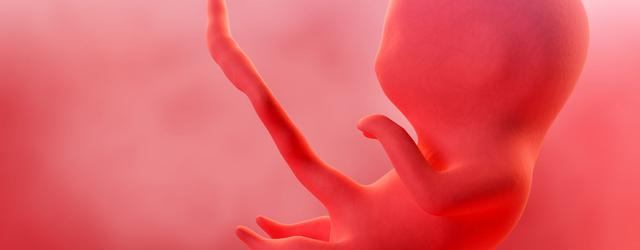

In der 5. Schwangerschaftswoche hat sich der Embryo bereits in der Gebärmutterschleimhaut eingenistet und die Organentwicklung nimmt Fahrt auf. Neben dem Herz, der Lunge und dem Darm beginnt nun auch die Entwicklung des Nervensystems und der Blutgefäße. Der Embryo hat ab dem 22. Tag einen Herzschlag, dieser ist jedoch meist erst in der 8. Schwangerschaftswoche auf dem Ultraschall sichtbar.

Die Form des Embryos ist oval und erinnert an ein kleines Ufo. Er besteht aus drei Keimblättern: dem Ektoderm, Mesoderm und Entoderm. In dieser Woche beginnt die Entwicklung der Organanlagen wie Herz, Lunge, Darm, Blutgefäße, Geschlechtsorgane und Nervensystem. Auch das Neuralrohr bildet sich, aus diesem entstehen später Kopf und Wirbelsäule.

Die Organentwicklung des Babys hat bereits begonnen, aber es ist noch zu früh, um diese auf dem Ultraschallbild zu erkennen. Das Herz, die Lunge, der Darm, Blutgefäße, das Bindegewebe und das Nervensystem entwickeln sich langsam aus den drei Keimblättern des Embryos.